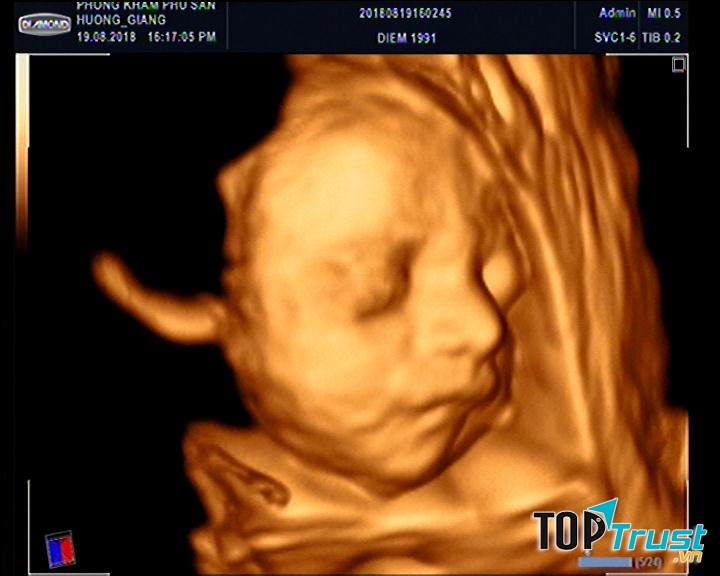

Hiện tại, bệnh viện đã được trang bị nhiều trang thiết bị y tế hiện đại như: MRI, DSA, siêu âm 3D, 4D, hệ thống xét nghiệm máy tự động đa thông số, x-quang kỹ thuật số, CT 64 lát cắt, máy siêu lọc máu, siêu âm tim gắng sức, hệ thống phẫu thuật nội soi,... góp phần trong chẩn đoán sớm và chính xác, cũng như điều trị. Từ những thiết bị hiện đại, Bệnh viện đã triển khai điều trị các bệnh lý mà trước đây phải chuyển lên tuyến trên như: Thay khớp háng, thay khớp gối, phẫu thuật Phaco, điều trị các bệnh lý can thiệp tim mạch, phẫu thuật nội soi các bệnh lý ở bụng và ngực, đặt máy tạo nhịp ngoài lồng ngực, điều trị nội khoa ung thư,.. Vì vậy, mọi người hoàn toàn yên tâm khi đến đây lựa chọn cho mình các dịch vụ tương ứng.

Khoa Sản Nhi là một trong những khoa được quan tâm hiện nay của bệnh viện với đội ngũ bác sĩ giỏi có trình độ chuyên môn cao và nhiệt tình tâm huyết. Bệnh nhân được chăm sóc chu đáo và hoàn toàn yên tâm với sự phục vụ tận tình của đội ngũ y, bác sĩ chuyên khoa, đa khoa, điều dưỡng giỏi chuyên môn, giàu kinh nghiệm, cùng sự hỗ trợ của hệ thống trang thiết bị hiện đại cho phép bệnh viện ứng dụng nhiều kỹ thuật y khoa tiên tiến trong chẩn đoán. Các dịch vụ như: khám thai; siêu âm 3D,4D; siêu âm, phát hiện dị tật thai nhi sớm; hỗ trợ sinh sản;..

- Siêu âm thai 3D, 4D.